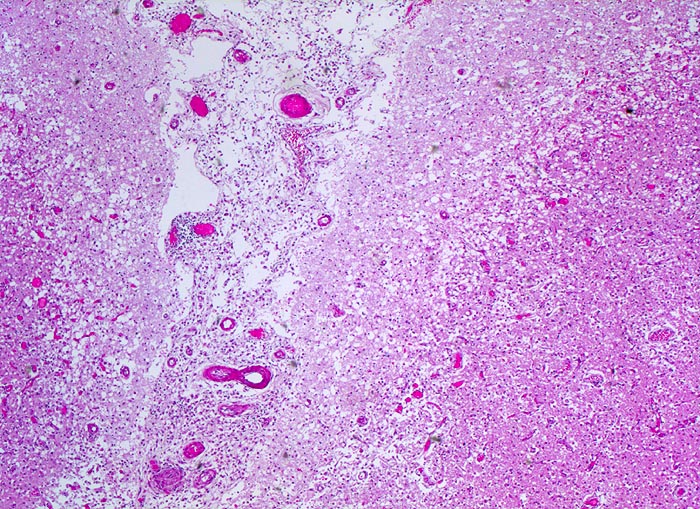

subakuter anämischer Hirninfarkt

vaskulär / Durchblutungsstörung

Hirn parietal

Spongiotische (=Ödem) Auflockerung der Hirnrinde (hellere Areale), Gefässneubildungen und Gefässhyperämie (hämorrhagischer Randsaum) im Randbereich der Nekrose mit unscharfer Mark-Rinden Grenze. Die Hirnhaut zwischen den beiden Windungen ist entzündlich infiltriert und enthält teilweise thrombosierte Gefässe.

Vor 7 Tagen Entwicklung eines Hemisyndrom links.

Anämische Hirninfarkte entstehen als Folge eines thrombotischen oder embolischen arteriellen Verschlusses. Es kommt zur lokalen Ischämie mit Blutleere (Entfärbung des Versorgungsgebietes = weisse Enzephalomalazie) im Versorgungsgebiet der verschlossenen Arterie. Meist entsteht eine Kolliquationsnekrose (gelb-weißes Zentrum, hämorrhagischer Randsaum).